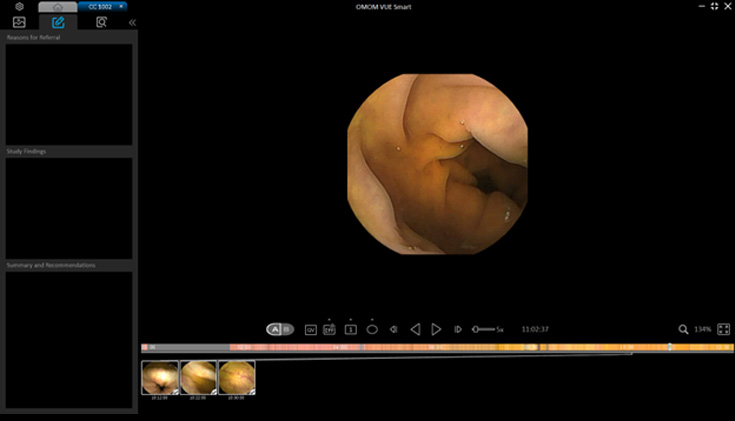

Vue Smart™

Wykorzystując zastrzeżone algorytmy sztucznej inteligencji, SmartScan przetwarza surowe pliki obrazów, usuwając do 90% nadmiarowości, identyfikując i oznaczając aż 16 rodzajów nieprawidłowości.

Tryb czytania SmartView odtwarza tylko obrazy pobrane przez Smartscan, pomagając nam szybciej poruszać się po całym filmie. Dzięki temu możemy przyspieszyć proces diagnostyczny.

Tryb czytania SmartView odtwarza tylko obrazy pobrane przez Smartscan, pomagając nam szybciej poruszać się po całym filmie. Dzięki temu możemy przyspieszyć proces diagnostyczny.